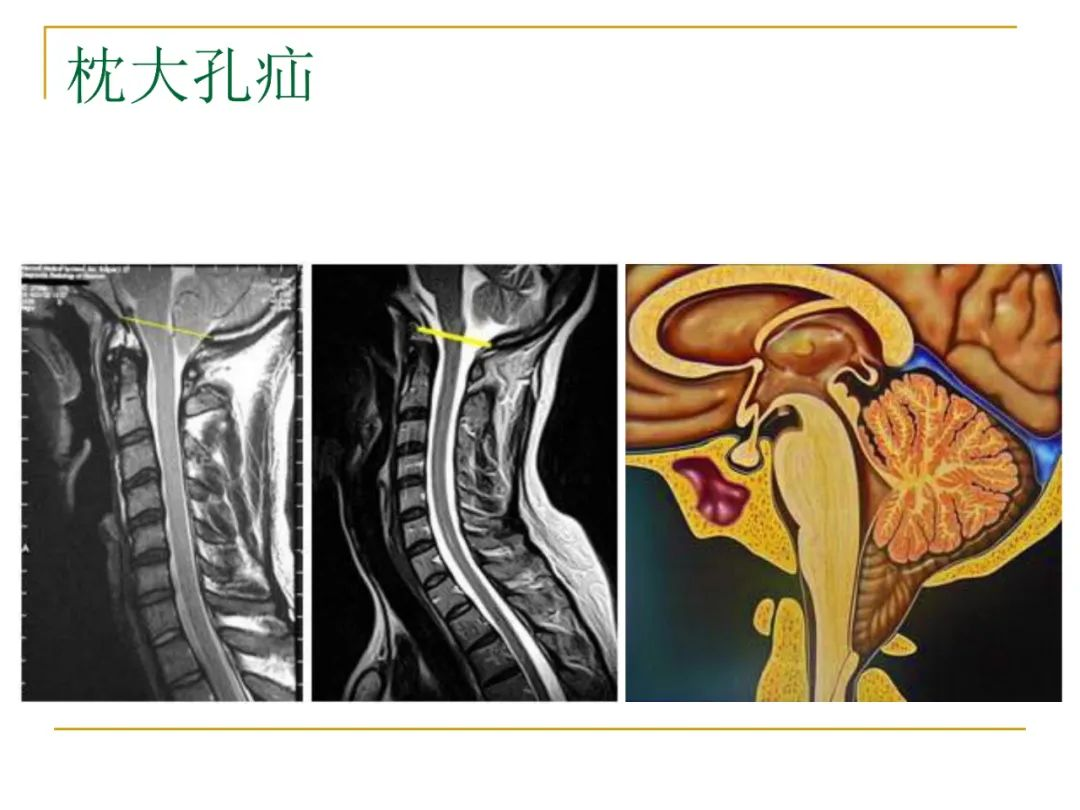

系统解剖实验的幻灯片 枕骨大孔

②枕骨大孔疝(transforamen magna herniation),为小脑扁桃体及延髓经

当小脑扁桃体疝入枕骨大孔时,阻塞了脑嵴液的循环,并且可能压迫脑干和

枕骨大孔疝可以压迫脑干的生命中枢,直接引起患者的死亡,情况非常危及